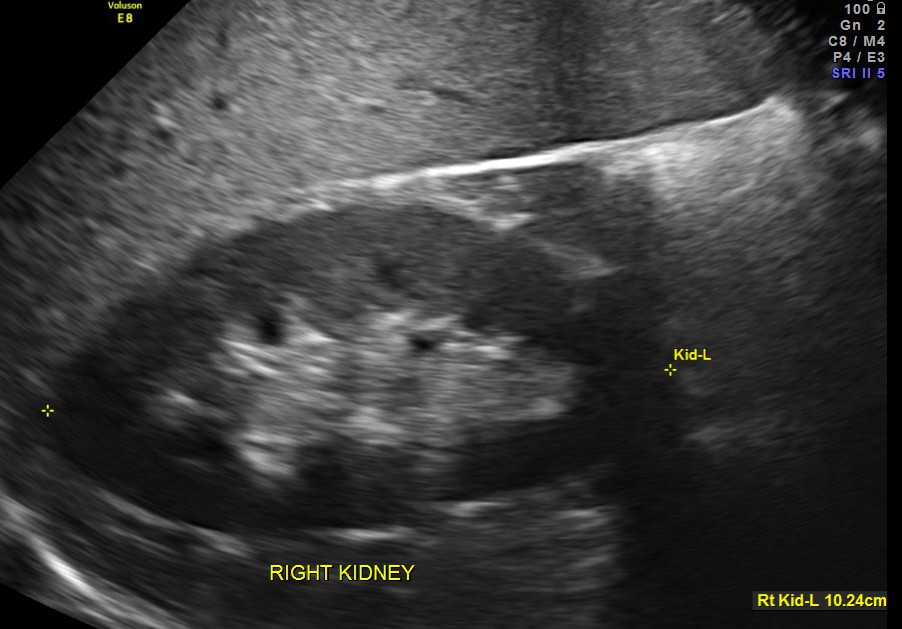

The scan was otherwise normal.